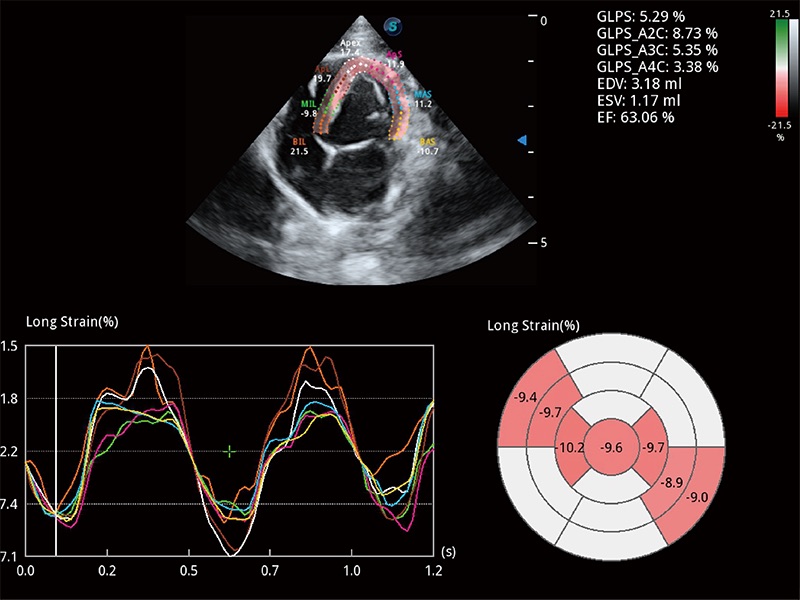

ProPet 80 配备了丰富的心脏探头群、先进的成像技术和专业的心脏测量工具,可帮助动物医生为不同体型和生理结构的动物提供心脏和心肌功能的全面评估。

实时用颜色表示心肌组织运动,观察和定量组织的运动情況,对快速检测与评估心肌的灌注和活性、电传导及心肌收缩和舒张功能等均能提供重要的诊断信息。

通过心肌识别技术与二维斑点追踪技术相结合,对心脏的超声图像进行量化分析。计算心肌17个节段的应变、应变率、速度、位移等,并通过牛眼图的形式进行呈现。

能够基于左心室壁追踪和辛普森法,自动计算射血分数,支持多个可移动点描迹,与手动测量相比,极大节省了动物医生的时间和精力。